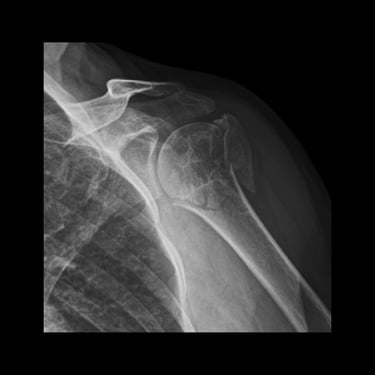

Paciente fémina de 70 años de edad, muy activa e independiente, presenta fractura de húmero proximal multifragmentada. Se opta por tratamiento quirúrgico en el cual se obtienen resueltados excelentes. Actualmente en fisioterapia y realizando actividades de la vida diaria sin limitaciones

FRACTURA DE HUMERO PROXIMAL